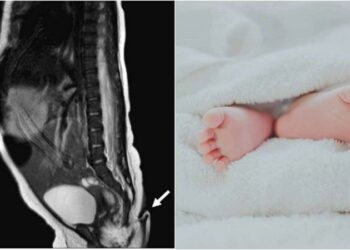

En el estado de Nuevo León, en México, se registró el nacimiento de una bebé con una cola que llegó ...